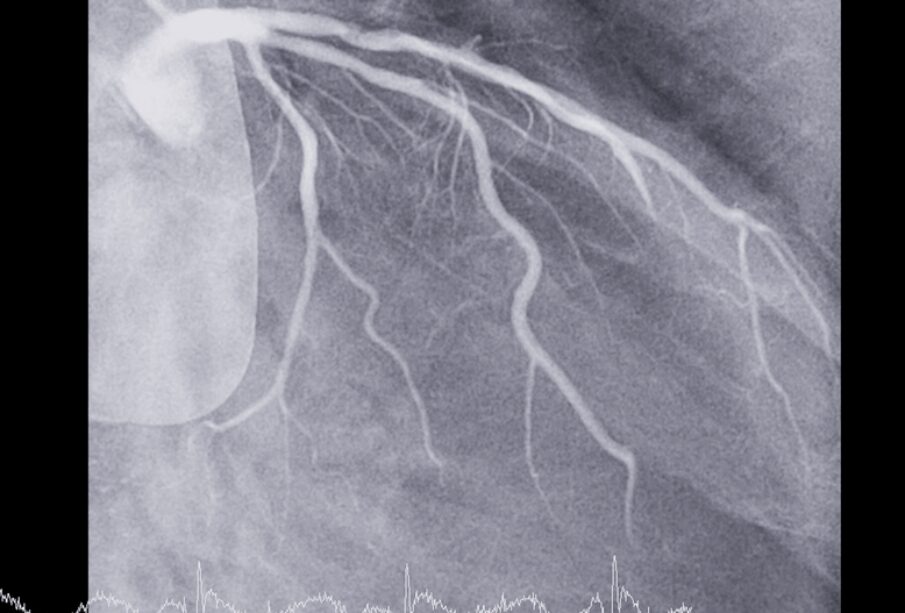

- Kraujagyslių kateterizacija (angiograma): Per kirkšnį ar koją į širdies kraujagysles įvedamas plonas vamzdelis – kateteris, per kurį suleidžiami kontrastiniai dažai. Rentgenograma po šios procedūros leidžia matyti kraujagyslių pažeidimus ar užsikimšimus. Dažniausiai atliekama po širdies priepuolio.